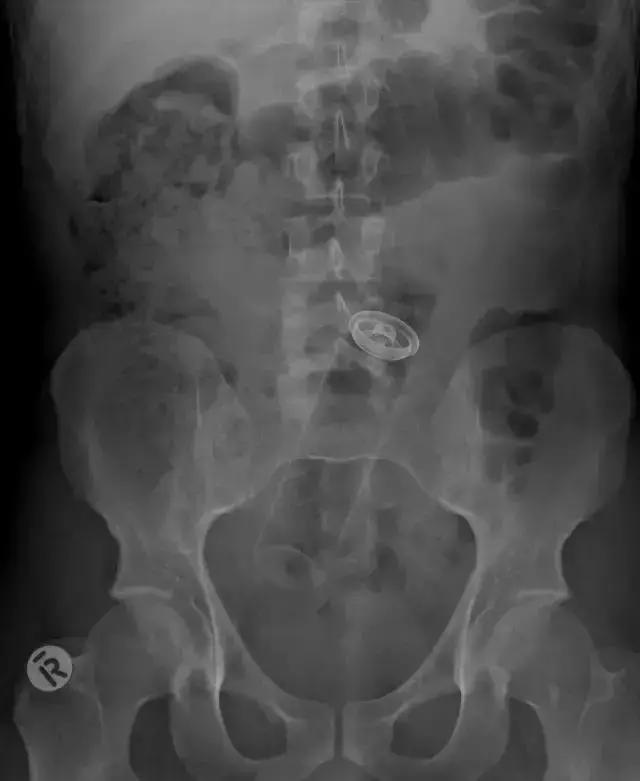

4、能看出是什么吗?这是小型的氧气罐